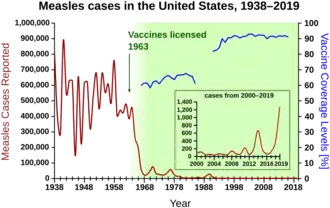

In the United States, measles affected approximately 3,000 people per million in the 1960s before the vaccine was available. With consistent widespread childhood vaccination, this figure fell to 13 cases per million by the 1980s, and to about 1 case per million by 2000.[117]

Before immunization in the United States, between three and four million cases occurred each year.[5] The United States was declared free of circulating measles in 2000, with 911 cases from 2001 to 2011. In 2014 the CDC said endemic measles, rubella, and congenital rubella syndrome had not returned to the United States.[119] Occasional measles outbreaks persist, however, because of cases imported from abroad, of which more than half are the result of unvaccinated U.S. residents who are infected abroad and infect others upon return to the United States.[119] The CDC continues to recommend measles vaccination throughout the population to prevent outbreaks like these.[120]

A resurgence of measles occurred during 2019, which has been generally tied to parents choosing not to have their children vaccinated as most of the reported cases have occurred in people 19 years old or younger.[133][134][135][136][137] Cases were first reported in Washington state in January, with an outbreak of at least 58 confirmed cases most within Clark County, which has a higher rate of vaccination exemptions compared to the rest of the state; nearly one in four kindergartners in Clark did not receive vaccinations, according to state data.[131] This led Washington state governor Jay Inslee to declare a state of emergency, and the state's congress to introduce legislation to disallow vaccination exemption for personal or philosophical reasons.[138] In April 2019, New York Mayor Bill de Blasio declared a public health emergency because of "a huge spike" in cases of measles where there were 285 cases centred on the Orthodox Jewish areas of Brooklyn in 2018, while there were only two cases in 2017. There were 168 more in neighboring Rockland County.[139] Other outbreaks have included Santa Cruz County and Butte County in California, and the states of New Jersey and Michigan.[137] As of April 2019, there have been 695 cases of measles reported in 22 states.[115] This is the highest number of measles cases since it was declared eradicated in 2000.[115] From 1 January, to 31 December 2019, 1,282 individual cases of measles were confirmed in 31 states.[116] This is the greatest number of cases reported in the U.S. since 1992.[116] Of the 1,282 cases, 128 of the people who got measles were hospitalized, and 61 reported having complications, including pneumonia and encephalitis.[116]

Following the end of the 2019 outbreak, reported cases have fallen to pre-outbreak levels: 13 cases in 2020, 49 cases in 2021, and 121 cases in 2022.[140]

In 1954, the virus causing the disease was isolated from a 13-year-old boy from the United States, David Edmonston, and adapted and propagated on chick embryo tissue culture.[171] The World Health Organization recognizes eight clades, named A, B, C, D, E, F, G, and H. Twenty-three strains of the measles virus have been identified and designated within these clades.[172] While at Merck, Maurice Hilleman developed the first successful vaccine.[173] Licensed vaccines to prevent the disease became available in 1963.[174] An improved measles vaccine became available in 1968.[175] Measles as an endemic disease was eliminated from the United States in 2000, but continues to be reintroduced by international travelers.[176] In 2019 there were at least 1,241 cases of measles in the United States distributed across 31 states, with over three quarters in New York.[177]